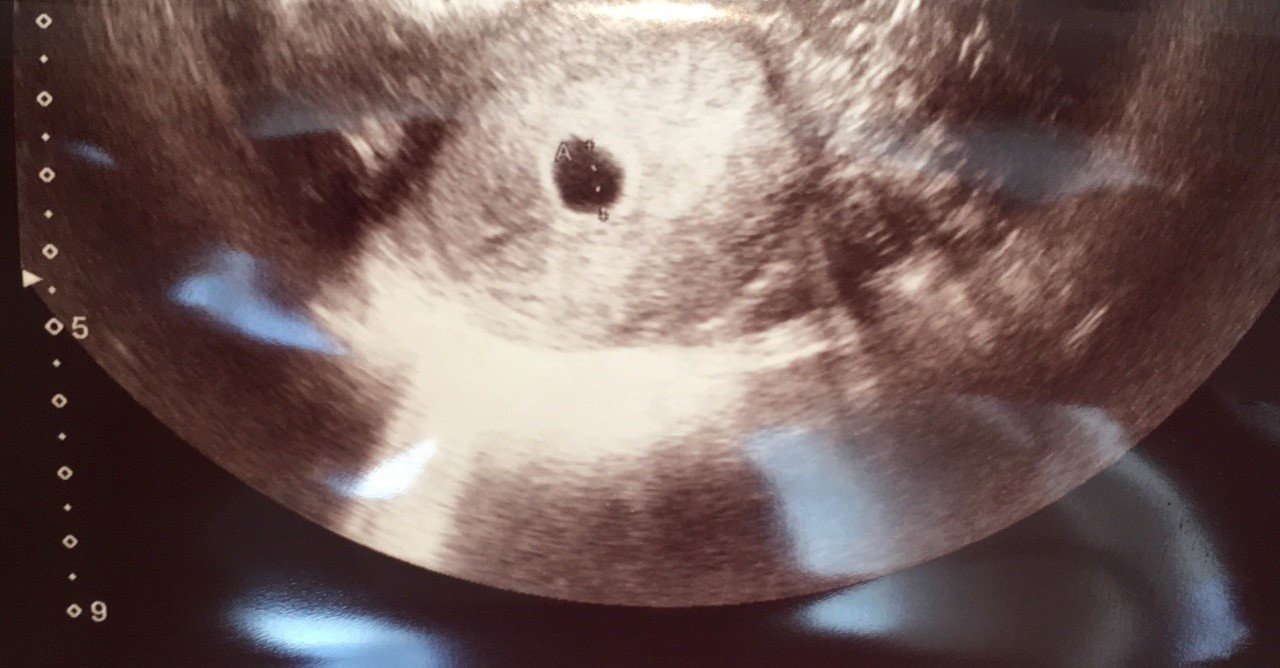

妊娠4週:超音波検査(エコー)で、胎嚢が見える! 妊娠4週は、子宮の中に胎嚢(たいのう)が見えてくるころです。 超音波検査の画面には子宮の中に黒い袋のように映ります。 胎嚢は赤ちゃんを包む袋! 英語では「Gestational Sac」、直訳すると「妊娠袋」です。 どちらも少々味気ないネーミングなので、「赤ちゃんの部屋」と呼んであげましょうか! このころ労働基準法 第35条第2項 前項の規定は、4週間を通じ4日以上の休日を与える使用者については適用しない。 労働基準法 施行規則 第12条の2第2項 使用者は、法第35条第2項の規定による労働者に休日を与える場合には、就業規則その他これに準ずるものにおいて、4日以上の休日を与えることとする4週間の起算日を明らかにするものとする。 労働基準法 施行規則 第12条 フリーターをやるより週休3日制(週4勤務)の正社員をやった方が面白いかもしれない どうも、しんま13です。 自分は就職した会社を一か月半で辞めて以来、一人暮らしをしながらずっとフリーターをやっています。 フリーター期間は実に8年。 なんで

妊娠2ヶ月 妊娠4週目 超音波で胎嚢確認 おやこ

妊娠4週 たまひよ 医師監修 妊婦の症状や体の変化 赤ちゃんの成長

妊娠4週目のエコー写真 胎芽や胎嚢 初期症状や流産のこと 妊娠初期 All About